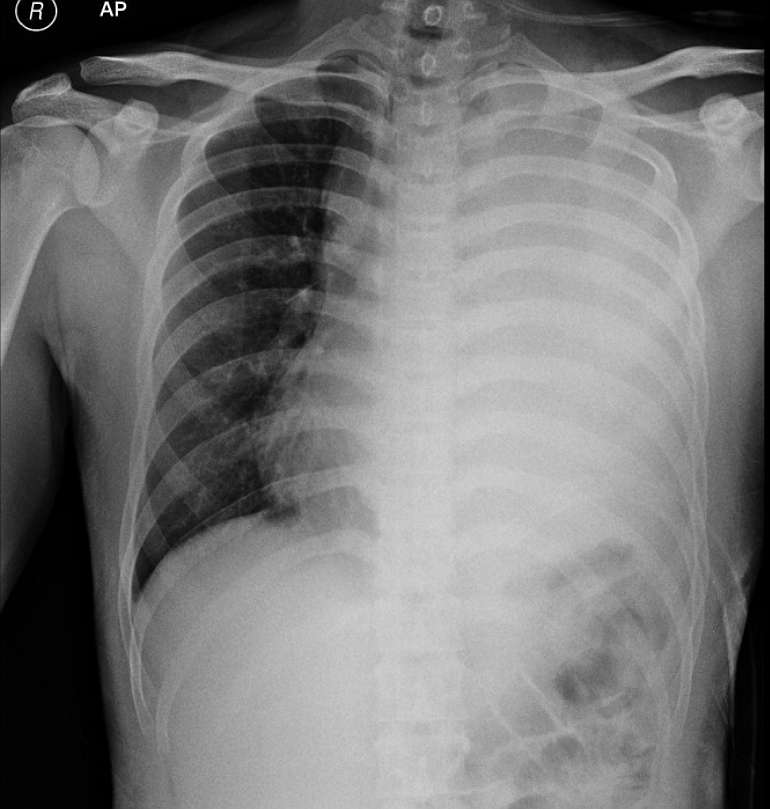

A 15-year-old male patient presented with a 3-months history of shortness of breath, decreased appetite, fatigue and fever. A chest radiograph revealed a massive left-sided pleural effusion. A chest tube was placed on the left hemithorax and the patient was sent to a referral centre.

What’s the diagnosis ?